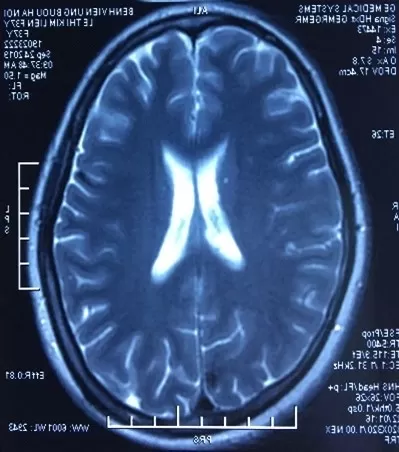

BN nữ L.T.K.L (SN 1987), nhập viện tại thời điểm tháng 07/2019 vì lý do co giật, yếu 1/2 người trái. Bệnh nhân xuất hiện các cơn đau đầu âm ỉ với tần suất tăng dần từ thời điểm trước khi nhập viện 4-5 tháng, đã đi khám tại một số bệnh viện và điều trị không giảm, bệnh nhân sau đó xuất hiện cơn co giật, được đưa vào cấp cứu tại BV Bạch Mai, hình ảnh chụp MRI sọ não cấp cho thấy các khối di căn lan toả 2 bán cầu, chủ yếu bán cầu não phải, hình ảnh cắt lớp vi tính ngực gợi ý tổn thương nguyên phát từ phổi. Bệnh nhân được giải thích tình trạng nặng, sau đó được chuyển sang BV Ung Bướu Hà Nội điều trị giảm nhẹ. Rất may mắn tại bệnh viện Ung Bướu Hà Nội, bệnh nhân được rà soát các tổn thương toàn thân và cuối cùng được sinh thiết hạch cổ làm chẩn đoán. Giải phẫu bệnh hạch cổ có kết quả di căn ung thư biểu mô tuyến nguồn gốc phổi, xét nghiệm giải trình tự gen cho kết quả dương tính với đột biến tái sắp xếp ALK. Bệnh nhân được tiếp cận điều trị thuốc kháng ALK thế hệ 2- Ceritinib, chỉ sau 1 tháng bệnh nhân hồi phục hoàn toàn các triệu chứng về thần kinh trung ương, đi lại vận động sinh hoạt như bình thường. Kết quả chụp lại MRI sọ não và CLVT ngực sau 02 tháng điều trị cho thấy hình ảnh đáp ứng sớm và ngoạn mục với liệu pháp nhắm đích.

Hình 5: tổn thương MRI não sau điều trị